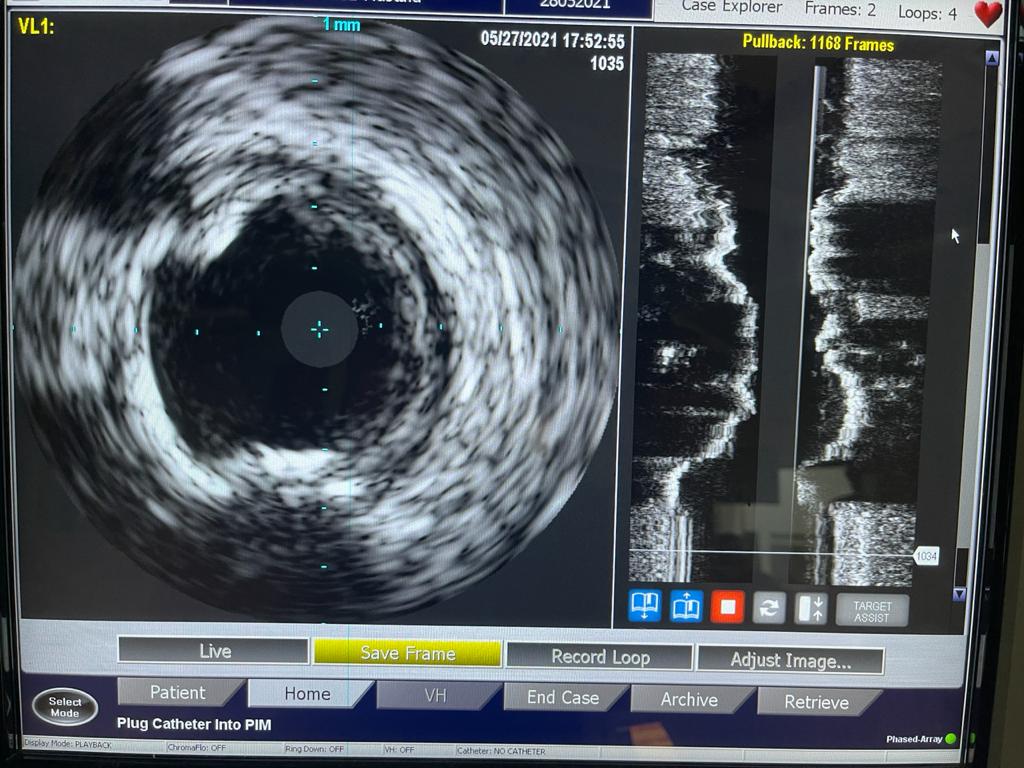

واستكملت أن الحالة الثالثة لمريضة تبلغ من العمر 70 عامًا، تعاني من قصور شديد بالشرايين التاجية للقلب وانسداد تام مزمن بالشريان التاجي الأيمن، إضافة إلى انسداد مزمن بالشريان التاجي الدائري الملنف وضيق شديد بالشريان الأمامي، ولها بنت مريضة من ذوي القدرات الخاصة، ولا تستطيع التغيب عنها لفترة طويلة، فتم علاجها على وجه السرعة عن طريق توسيع للشرايين بالبالونات العادية والدوائية إلى جانب تركيب دعامات دوائية لها باستخدام أحدث التقنيات العالمية بنجاح، واستطاعت الخروج من المستشفى في أقل من 24 ساعة لتعود إلى بيتها وابنتها التي تحتاج إلى رعايتها.

وتابعت الهيئة أنه قام بإجراء العمليات للمرضى الثلاثة في يوم واحد، فريق من أمهر الأطباء الأخصائيين والاستشاريين في علاج أمراض القلب والقساطر القلبية، يضم، الدكتور طارق رشيد أستاذ القلب والقسطرة وخبير حالات الانسداد المزمن للشرايين التاجية ورئيس قسم القسطرة القلبية بمستشفى النصر التخصصي، والدكتور ياسر صادق استشاري القلب وخبير القسطرة القلبية، الدكتور أمير البسطويسي استشاري جراحة القلب والصدر، الدكتور أحمد شبل استشاري القلب والقساطر التداخلية، الدكتور محمد علم الدين استشاري القلب والقسطرة العلاجية، الدكتور محمد لبيب استشاري جراحة الأوعية الدموية، وإخصائي علاج أمراض القلب والأوعية الدموية الدكتور معتز سلامة و الدكتور محمد عطا، أخصائي علاج أمراض القلب والقسطرة العلاجية الدكتور مصطفى رفعت، الدكتور أحمد عبد الرؤوف أخصائي التخدير بالمستشفى.